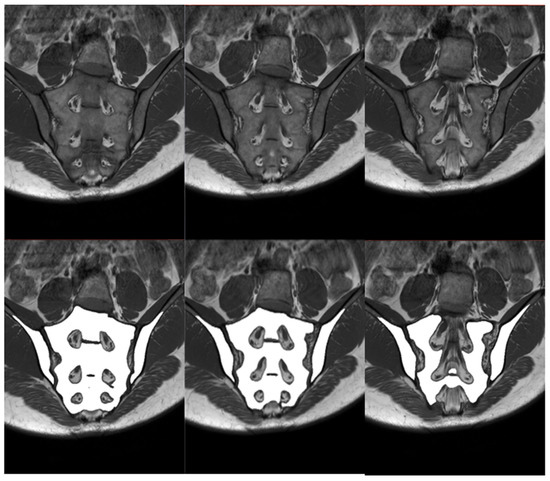

Figure 3.

Scoring scale used in the study. The evaluation involves six slices of each examination. (a) Graphic illustrating the division of the SIJ into quadrants: R1—right iliac (upper), R2—right sacral (upper), R3—right iliac (lower), R4—right sacral (lower), L1—left iliac (upper), L2—left sacral (upper), L3—left iliac (lower), L4—left sacral (lower). Depth and intensity rating details (SPARCC scale) are provided below the graphic. (b) Quadrant division illustrated on the T1 sequence. (c) Corresponding quadrant division illustrated on the STIR sequence.

In order to compare the performance of the improved algorithm depending on the technical correctness of the MRI of the sacroiliac joints, it is necessary to perform both manual and automatic bone segmentations. Therefore, it was decided to manually segment the iliac and sacral bones and then evaluate their agreement with the segmentations created by the algorithm. The area of the right and left iliac bones, as well as the sacrum, were manually labeled on consecutive slices of the T1-weighted sequence by one researcher. The segmentations were prepared manually with the 3D Slicer (version 4.11.20210226) program and then verified by two other members of the research team. After the verification, it was stated that the created segmentations cannot be more accurate and can serve as a reference for segmentations performed by the algorithm. The establishment of reference segmentation considerably simplifies the process of comparing algorithm performance, as it provides more tools that can assess the compatibility of human and artificial intelligence. The compatibility of both segmentations was evaluated by several means. Initially, to have all bone segmentations manually reviewed one by one by the researchers, a proprietary scale was introduced to assess compliance. The scale is shown in Figure 3 and was based on the SPARCC scale. In this visual scale, each examination can receive a maximum score of 48 points. Only six slices that represent the largest surface of the SIJs are selected and afterwards evaluated. Each SIJ is divided into quadrants. In each quadrant, the correspondence of manual and fully automated segmentation is evaluated; if both segmentations correspond, one point is granted. Secondly, the Dice coefficient (DC) is calculated as follows: